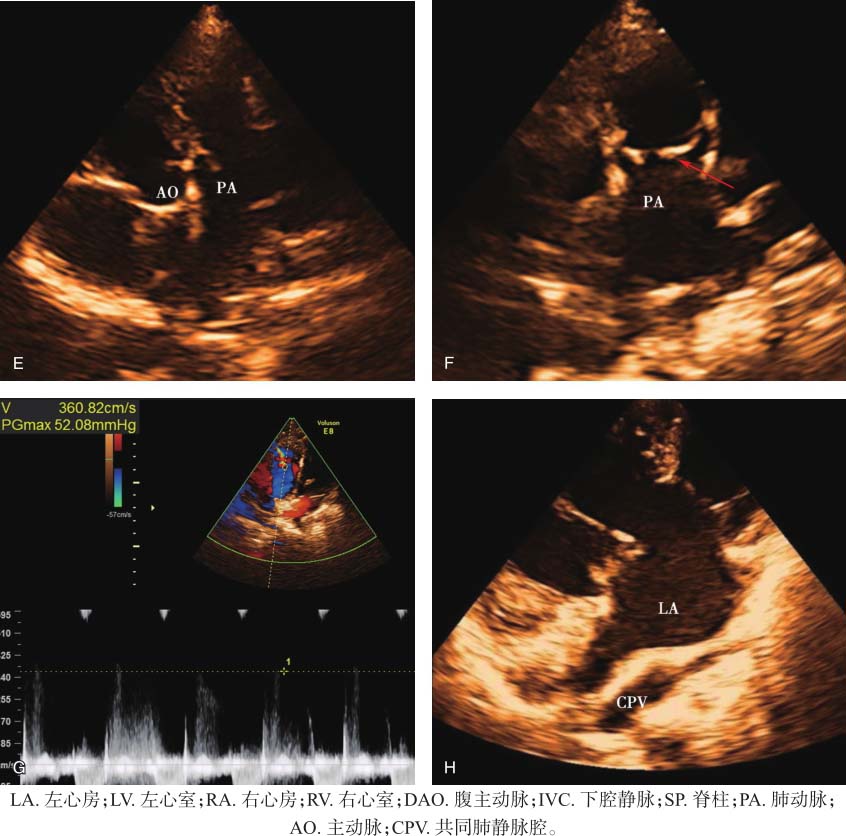

右心、左心房扩大。室间隔与左心室室壁厚度正常,运动幅度正常。房间隔下部至室间隔上部可探及宽约40mm回声失落,探及共同房室瓣环及共同房室瓣启闭,前桥瓣腱索骑跨,系于室间隔右心室面。流出道切面见肺动脉和主动脉均发自解剖学右心室,肺动脉在左,主动脉在右,肺动脉瓣增厚,回声增强,开放受限。左心房房壁未探及肺静脉切迹,其后方探及四支肺静脉均引流入共同肺静脉腔。主动脉弓降部未见明显异常。心包无异常。见图13-1。

图13-1 患儿超声心动图表现

A.上腹部横切面显示腹主动脉和下腔静脉均位于脊柱左侧,下腔静脉在前,腹主动脉在后;B.四腔心切面显示十字交叉结构消失,房间隔下部至室间隔上部可探及回声失落,并见共同房室瓣启闭;C.四腔心切面显示前桥瓣腱索骑跨,并系于室间隔右心室面(箭头);D.剑突下切面瓣口水平心室短轴切面显示共同房室瓣启闭;E.流出道切面显示肺动脉和主动脉均发自解剖学右心室;F.肺动脉瓣增厚,回声增强,开放受限,呈圆顶征(箭头);G.舒张期肺动脉瓣反流速度约360.82cm/s,估测平均肺动脉压约52.08mmHg;H.左心房房壁未探及肺静脉切迹,左心房后方探及四支肺静脉引流入共同肺静脉腔。

上腹部横切面显示水平肝,无脾,腹主动脉和下腔静脉位于脊柱同侧,由此可判断患者为右心房异构。二维超声显示四腔心切面十字交叉结构消失,房间隔下部至室间隔上部可探及回声失落,无正常的相互独立的左右心室流入道,探及共同房室瓣环和共同房室瓣启闭,前后桥瓣之间未粘连,前桥瓣腱索系于室间隔右心室侧,可诊断为完全型心内膜垫缺损,Rastelli分型为B型。主动脉和肺动脉起始部交叉包绕现象消失,二者均发自右心室,起始部平行走行,诊断为DORV,且肺动脉瓣存在狭窄。对右心房异构患者应特别关注是否存在肺静脉异位引流,重点观察左心房房壁是否有肺静脉切迹,是否存在肺静脉腔。